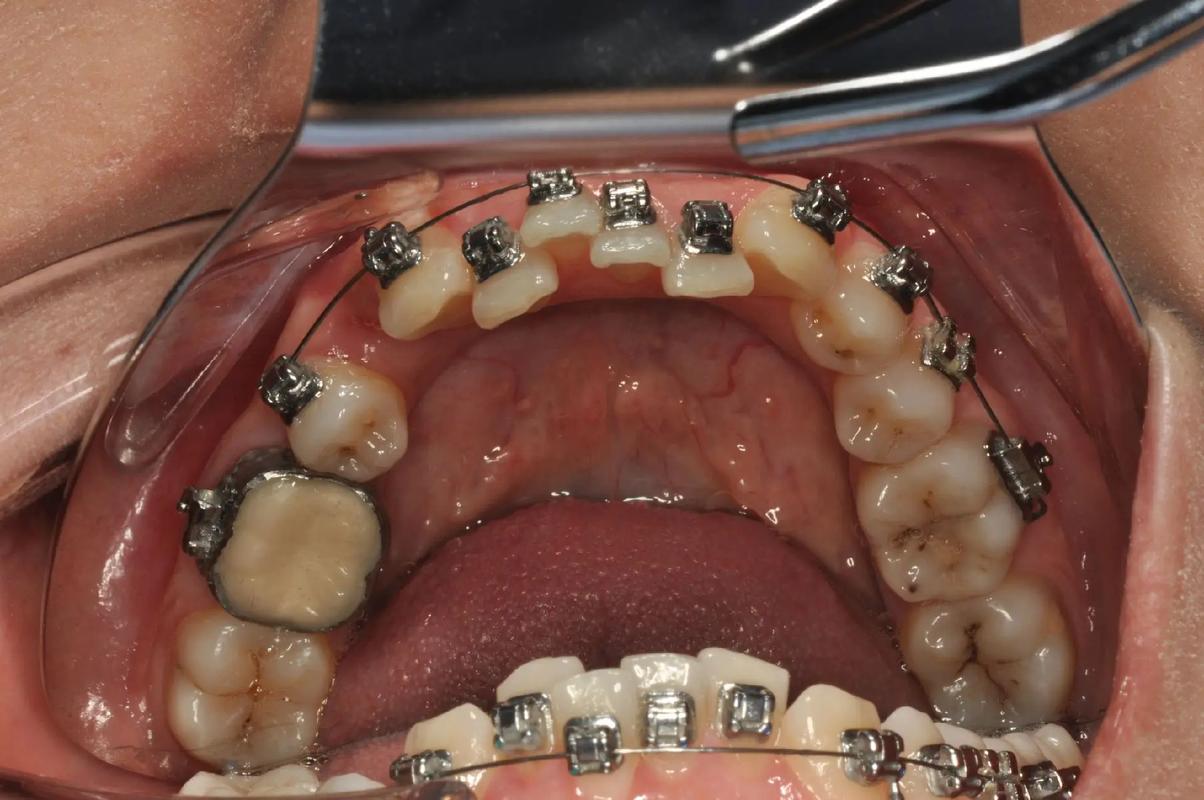

带环(又称“带环”或“颊面管带环”)是固定矫治器的重要组成部分,通常由不锈钢或贵金属制成,呈环状,紧密粘接在磨牙(如第一磨牙)的牙冠上,其主要作用包括:为矫治弓丝提供稳固的支抗点,传递矫治力,辅助牙齿移动;部分带环上焊接有颊面管、拉钩等附件,用于放置弓丝、结扎丝或橡皮圈,实现复杂的牙齿移动(如扭转、压低、伸长等),带环的粘接需经过严格的隔湿、酸蚀、涂粘接剂等步骤,确保与牙面密合,避免脱落或边缘渗漏,粘接后初期,患者可能感觉异物明显或轻微咬合不适,通常1周内可逐渐适应,需注意避免啃咬硬物(如坚果、骨头)、用带环侧咀嚼过硬食物,以防带环松动或脱落;同时加强口腔清洁,使用牙缝刷或冲牙器清洁带环边缘,防止菌斑堆积引发龋齿或牙周炎。